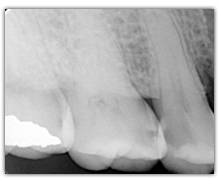

Does SOPROLIFE generates « False alerts »?

When SOPROLIFE generates a red fluorescence in a fissure, it is either due to a caries or to organic deposits. In this case a cleaning (pounce bag, air abrasion linked to Na bicarbonate ) is advised only in the suspicious fissure in order to avoid a falser alert.